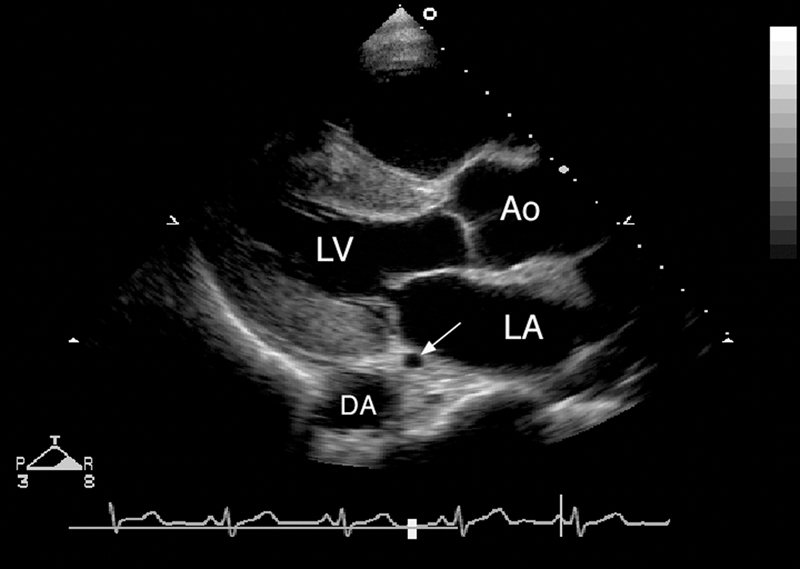

فحوصات تشخيصية لبعض امراض القلب والشرايين التاجية